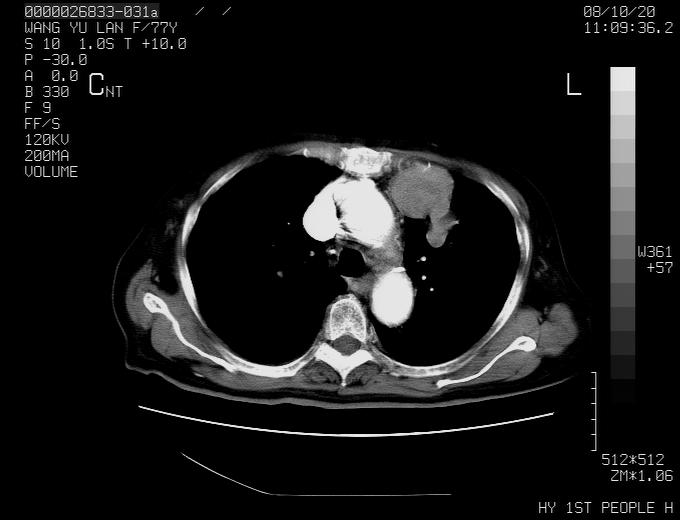

女性,77岁,胸部疼痛半月。左上肺团块影,本人考虑血管畸形,请分析

纵隔有多个淋巴结肿大,提示周围型肺癌并转移可能性大。

动脉期未见大血管同步强化,首先考虑周围型肺癌

动脉期病灶近中线侧可见星芒状与大血管同等强化密度,支持考虑血管畸形伴血栓形成,动脉期不曲型,不除外周围型肺癌

1、考虑avm可能性大。2、纵隔有肿大淋巴结,左肺上叶有炎性病变,不排除肺癌并转移可能。